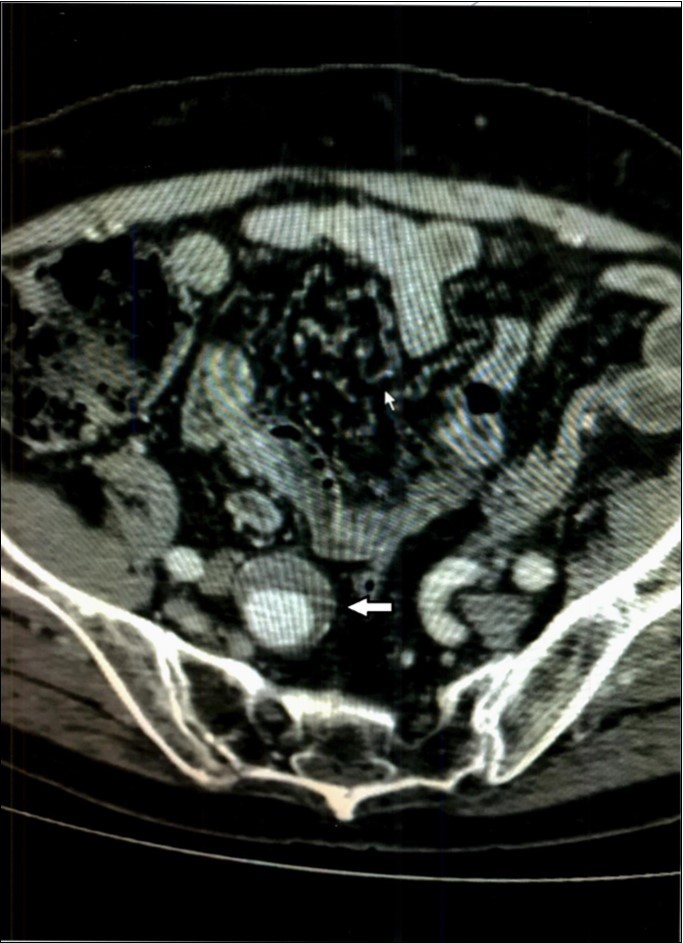

A 66 year old man was admitted to Christ Hospital in Jersey City, New Jersey, complaining of abdominal and back pain and weakness of at least one month duration. He had lost 40lbs of weight. Physical examination revealed mild mid abdominal tenderness and mental confusion. The temperature was 97.9. White blood count was 10.3 thousand per microliter. Computed tomography of the abdomen showed a 1.5 x 1.6 centimeter aneurysm of a branch of the superior mesenteric artery surrounded by some “inflammatory” reaction, Figure 3. Small stones were noted in the gall bladder. Immediate percutaneous embolization of the aneurysm was performed. CT scan of abdomen was “normal” before the present admission.

Figure 3.Case 3 – Superior Mesenteric Artery Branch Aneurysm surrounded by a halo.

In our second patient, Case 2, in addition to the aneurysm, the CT scan indicated “probable” bleeding, Figure 2, without any sign of systemic bleeding or infection, clinically or in the hemogram. The blood cultures were normal six days after treatment. White blood cell counts were normal and only mild anemia was present. Therefore, it is doubtful the aneurysm was mycotic. The “halo” around the aneurysm can be interpreted as pressure effect of the enlarging aneurysm on the surrounding tissues.